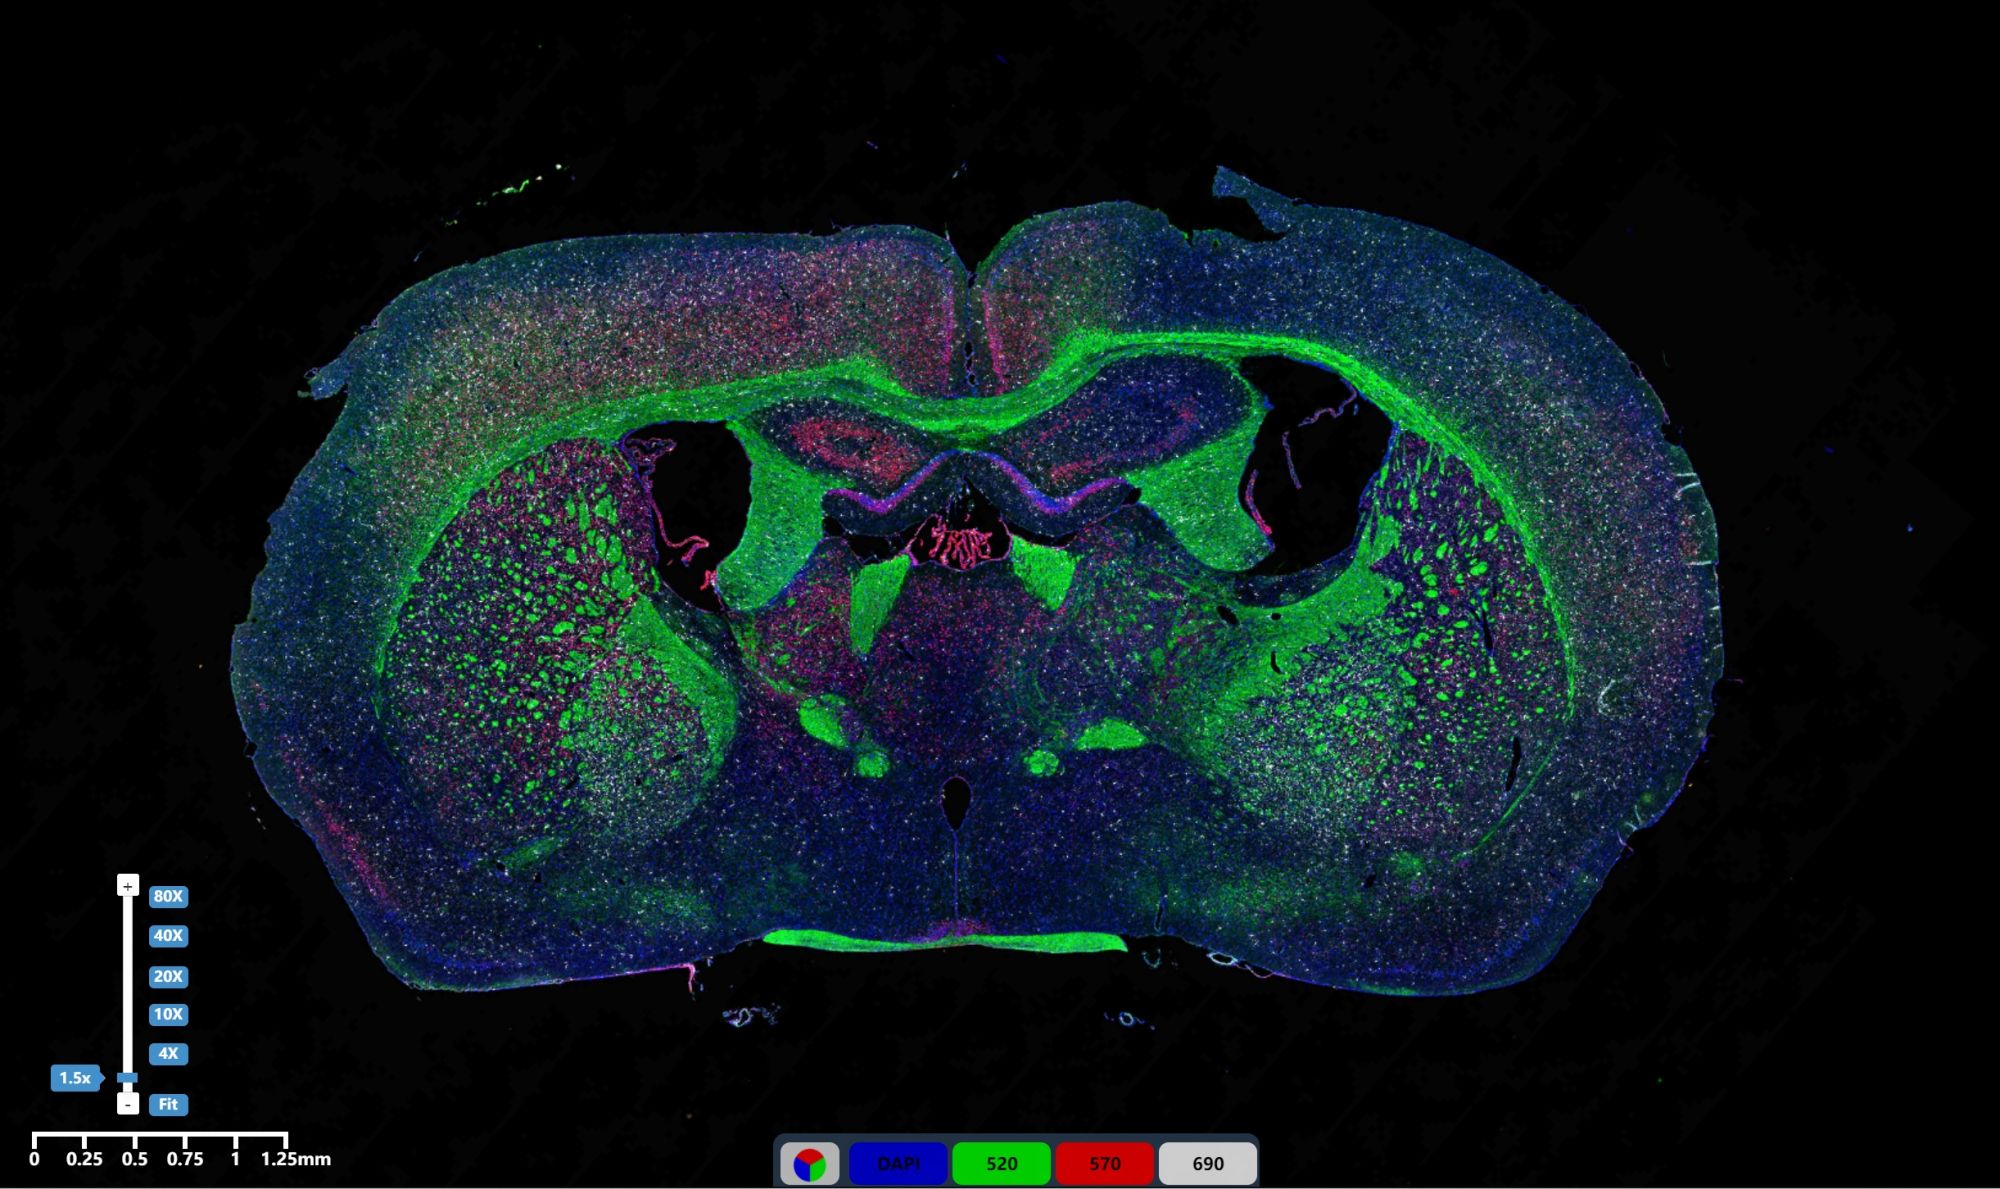

免疫熒光三標腦組織2

IF免疫熒光

992

免疫熒光三標腦組織

760